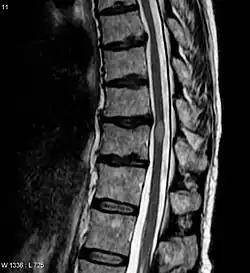

MRI image of a patient with transverse myelitis, one of the diagnostic criteria for NMOSD

NMOSD is diagnosed using consensus clinical criteria, which have undergone multiple revisions, most recently in 2015.[32][33]